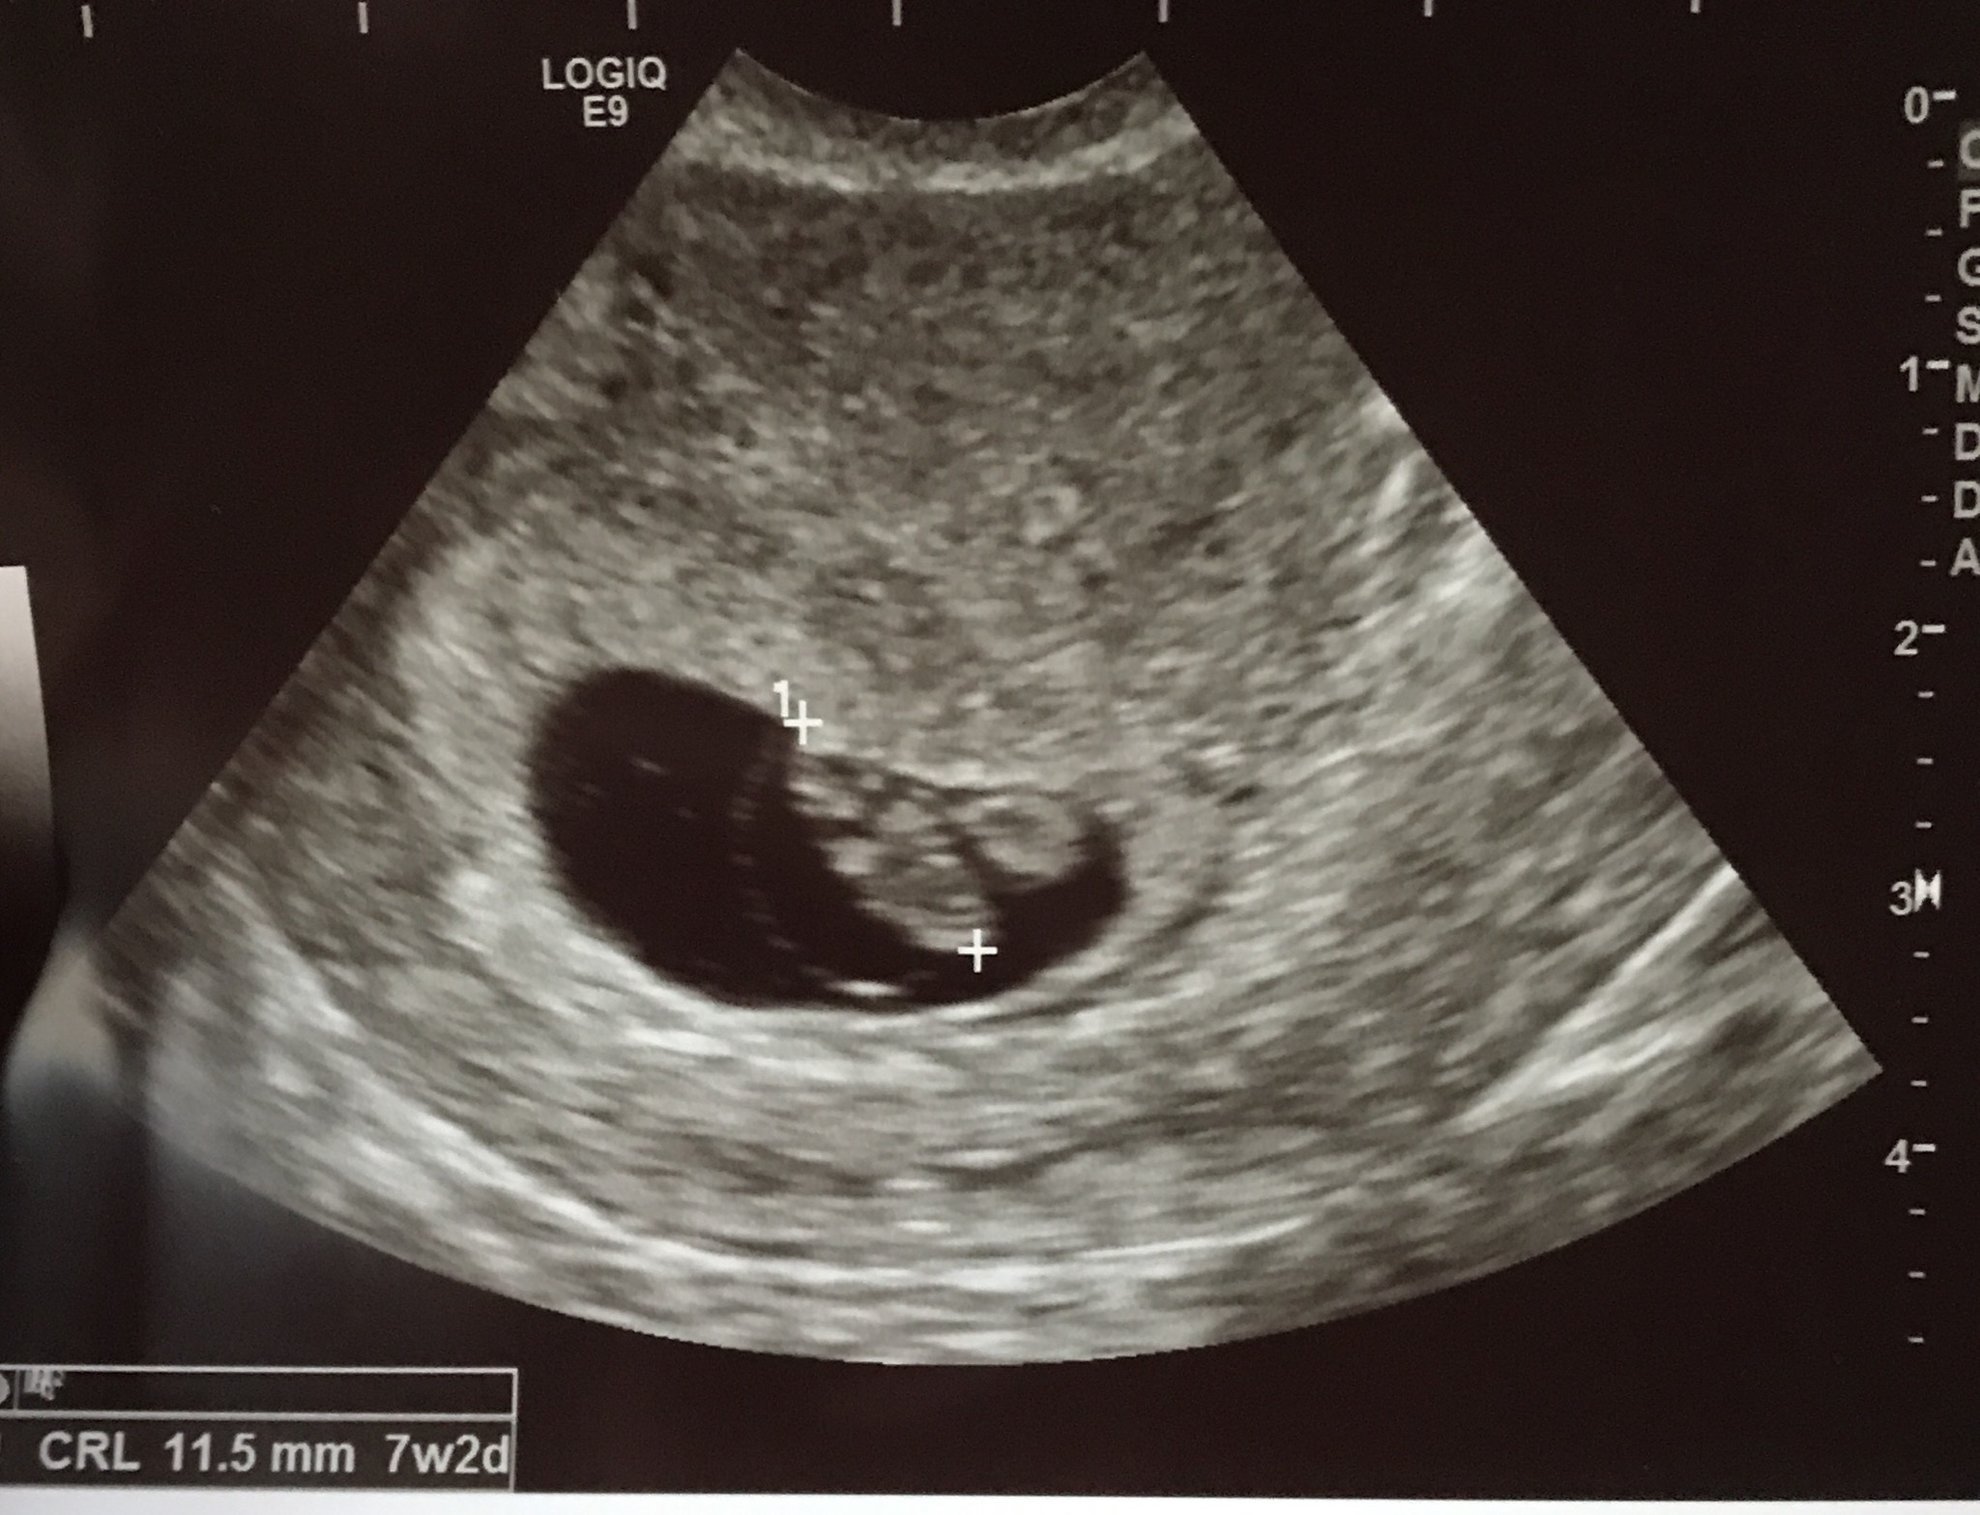

I might be biased, but how cute!!! You can see its little arm buds! I am 7w5d, but the baby measured at 8w1d. Bpm was 171. So far so good! Today was such a happy day!